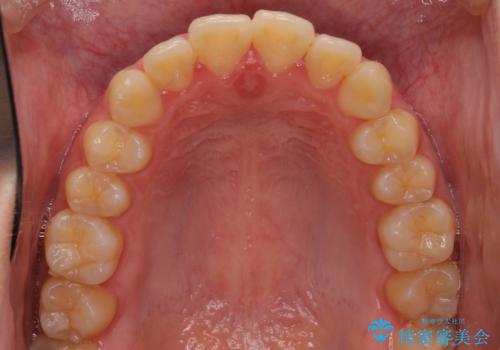

- 口元が出てるのが気になるとのことで来院されました。

歯のがたつきはあまりなかったのですが、口唇が閉じずらく、口元の突出感が確認できました。

上下左右の歯を1本ずつ抜歯して、そのスペースを利用して口元を引っ込める計画としました。